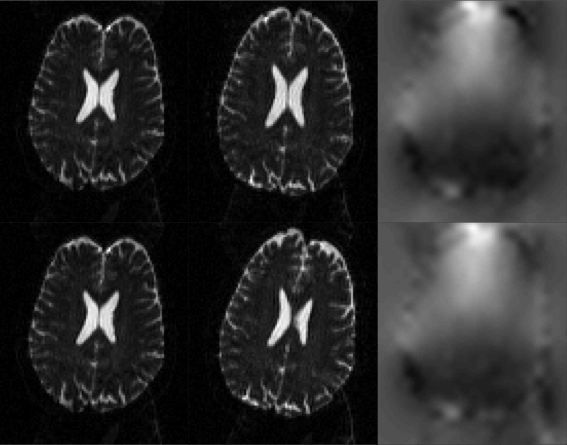

If instead using the true field for the GE-EPI images one can see below that the corrected images also look good. But looking closely one can see that in the areas of severe signal modulation it doesn't do quite as good a job (of matching the intensities) as the "faulty" field. Hence it is easy to see why topup would find the "faulty" field.

![]() |

| The top row shows the true field and the resulting corrected GE-EPI images. Note how the outlines of the brains look similar, indicating that the distortion correction has been successful. Note also that the intensities inside the brain are quite different, with the A->P image having more signal dropout posterior of the peak in the off-resonance field while in the P->A image it is mostly anterior of the peak. This indicates that the signal modulation is dominated by the gradient (in the off-resonance field) along the PE-direction, which leads to a shift in echo time. The bottom row shows the "faulty" field, that which was estimated from the GE-EPI image pair, along with the resulting corrected images. Note how topup has "successfully" managed to reduce the difference in signal modulation, leading to an estimated field that is vastly different to the truth. |